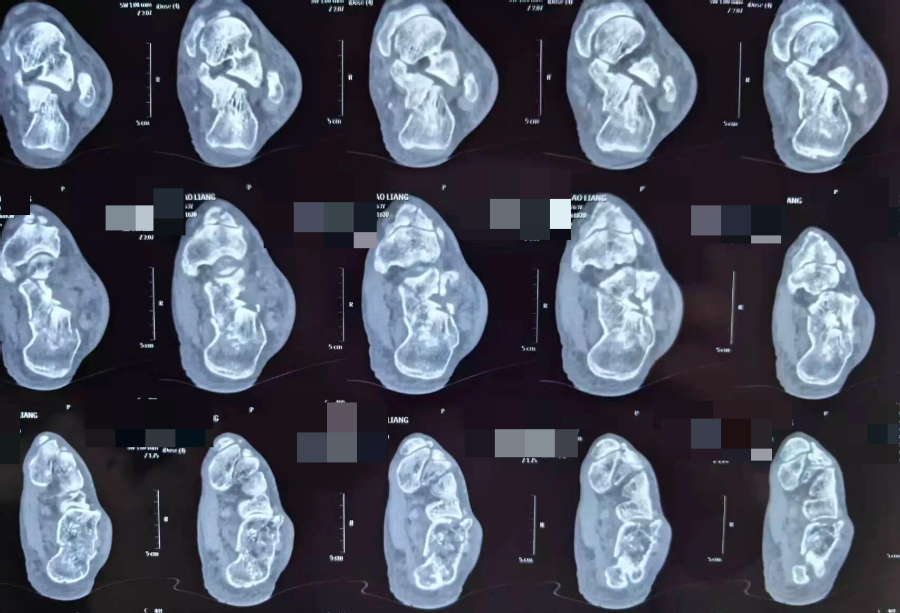

术前

日前,一名高处坠落伤致左侧跟骨粉碎性骨折的患者入院。骨三科团队经充分术前讨论,为其量身定制微创手术方案。术中在X光精准引导下,经皮撬拨复位骨折块,以空心螺钉稳固固定,出血极少、创伤小。术后患者恢复良好,早期即可开展功能锻炼,避免了传统大切口带来的并发症隐患。